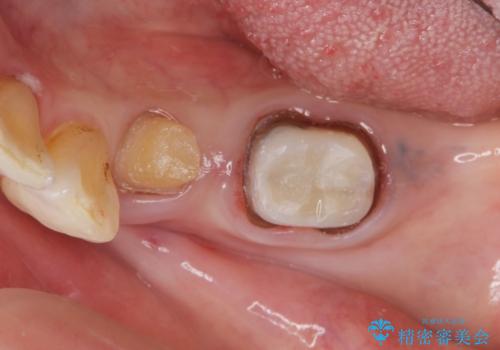

- 左下の大臼歯(6番)の根の治療を行いました。

左下6番の根管治療は六本木院の林院長にお願いしています。

左上56間が狭かったため、写真にはないですが、セパレーションを2回ほど行い、歯根間距離を広げてから処置を行っています。

歯と歯の間(特に歯根と歯根の間)が異常に狭いと歯型が正確にとれない上に歯間ブラシも入らないような歯の形態になり、セルフケアに支障がでてきます。

そのまま無理やり歯型を取って製作するよりも、ご自身で清掃ができる形態にできるため、長期的な予後が期待できます。